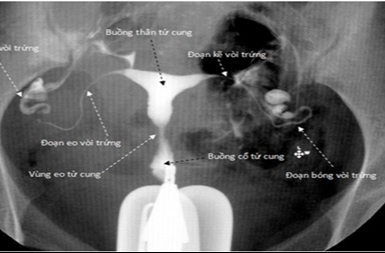

Chụp X quang tử cung vòi trứng, còn được gọi là chụp X quang tử cung và phần phụ, là một phương pháp chẩn đoán hình ảnh trong y học được sử dụng để xem xét và đánh giá tử cung và vòi trứng ở phụ nữ.

Chụp X quang tử cung vòi trứng là một trong những phương pháp chẩn đoán hình ảnh nhằm xem xét và đánh giá tình trạng sức khỏe của tử cung và vòi trứng ở phụ nữ. Tuy nhiên vẫn còn nhiều người chưa biết rõ những trường hợp nào thì cần thực hiện phương pháp này. Vậy chụp X quang có vai trò và tầm quan trọng như thế nào trong việc chẩn đoán các bệnh lý liên quan đến tử cung và vòi trứng?